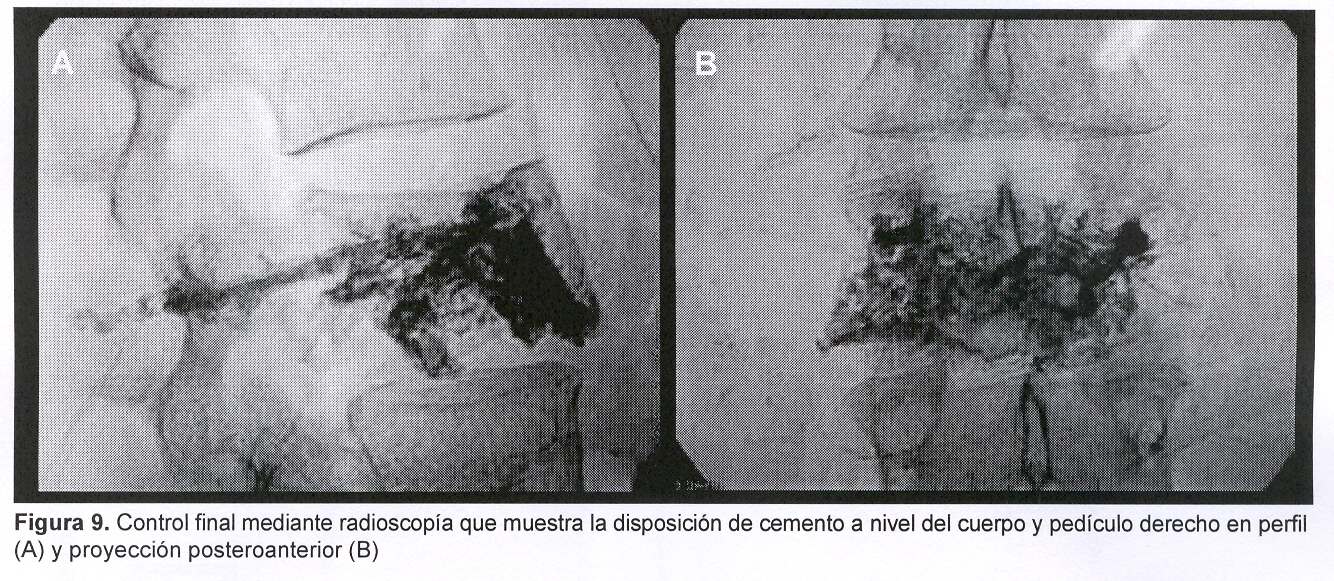

Se procedió a realizar vertebroplastia percutánea de L3 bipedicular mediante técnica ya descripta utilizando bario como contraste (figura 9).

La muestra obtenida de tejido patológico fue analizada y se concluyó que se trataba de una metástasis de tumor primitivo de mama. La paciente mejoró del dolor raquídeo en forma inmediata luego de la inyección de cemento. Comenzó a deambular sin dolor a las 24 horas del tratamiento.